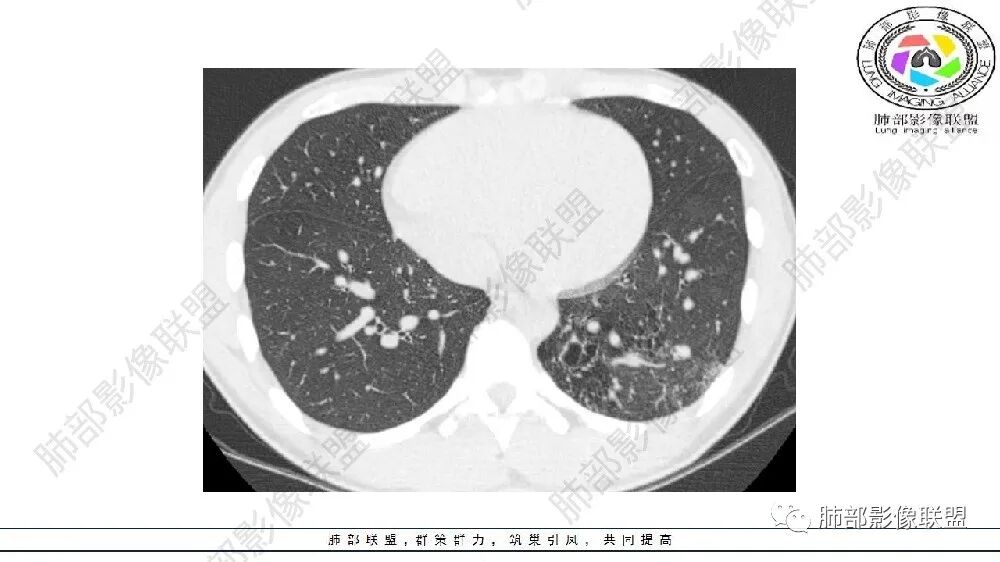

左肺下叶多发大小不等囊腔,周围伴有磨玻璃影,考虑CCAM伴感染。

左肺下叶多发大小不等囊腔伴周围磨玻璃影,可见血管增粗,似与胸主动脉相连,考虑肺隔离症,鉴别CPAM。

左肺下叶多发大小不等囊腔,囊壁略厚。周围见片状高密度影,边缘模糊不清,考虑CCAM伴感染,鉴别隔离症

左肺下叶多发囊腔、结节,及磨玻璃密度影,考虑肺隔离症,鉴别CCAM

左肺下叶多发大小不等囊腔,部分有粘液栓,周围伴有磨玻璃影,左肺下叶基底干支气管未见,双肺尖可见多发局限性透亮区,青年男性,考虑先天性气道或肺部发育畸形,支气管闭锁?CPAM?鉴别肺隔离症。

左肺下叶多发薄壁囊性病灶,血管贴边,并多发增粗的血管,还有一些斑片影,磨玻璃影;两肺尖也有薄壁囊性病灶;病史咳嗽咳痰,痰中带血,跟老师们考虑肺隔离症伴感染,鉴别LIP

左肺下叶多发囊腔,粗大血管影,隔离征可能,鉴别气道畸形。

常规思路: 20岁,肺部出现低密度病灶:多半要考虑先天性病变;其次就是坏死空洞。先天性:肺气肿、囊腺瘤样畸形、闭锁、隔离、支气管扩张,这些病灶符合肺气肿,低密度,胸膜下,无壁。

这些有高密度影,有痰中带血,首先警惕感染或支气管动脉破裂出血(多见于支气管扩张)

可见囊状影、管状影,附近血管明显增粗,似乎与肺动脉不相连

闭锁?附近没有大片肺气肿,不符合。为啥没有一元论?因为上肺病灶与左下叶病灶表现完全不同,一个是单纯低密度影,无壁;一个是管状+血管畸形

估计上肺病灶不会处理,所以忽视掉

主要观察左下叶病灶,应该是做过手术或明确了血管与主动脉关系,就目前的表现而言还是更支持隔离:肺动脉、支气管分支似乎没进入病灶区,这是隔离或体动脉供血的特点。囊腺瘤样畸形,按理肺动脉及支气管照样进入这个区域才对;需要重建观察这些血管、支气管才好明确